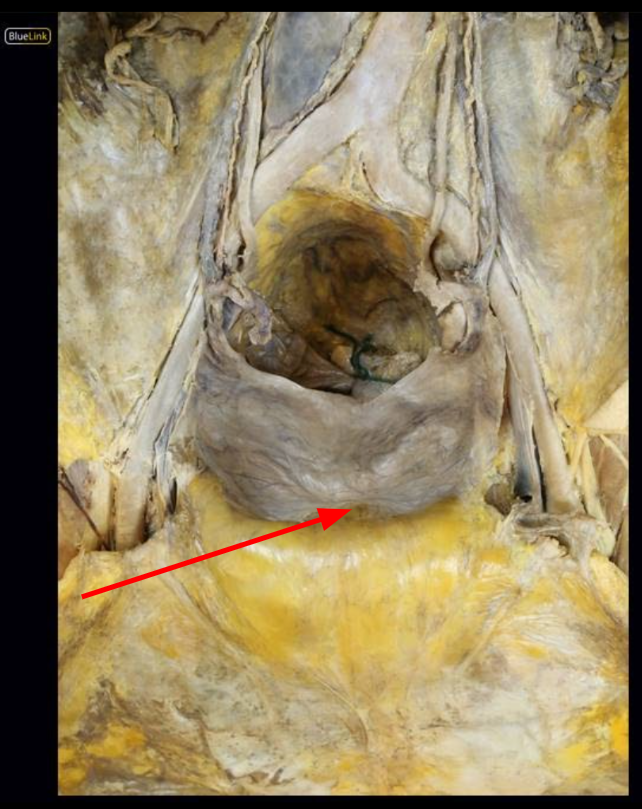

Pelvic Diaphragm

Levator ani